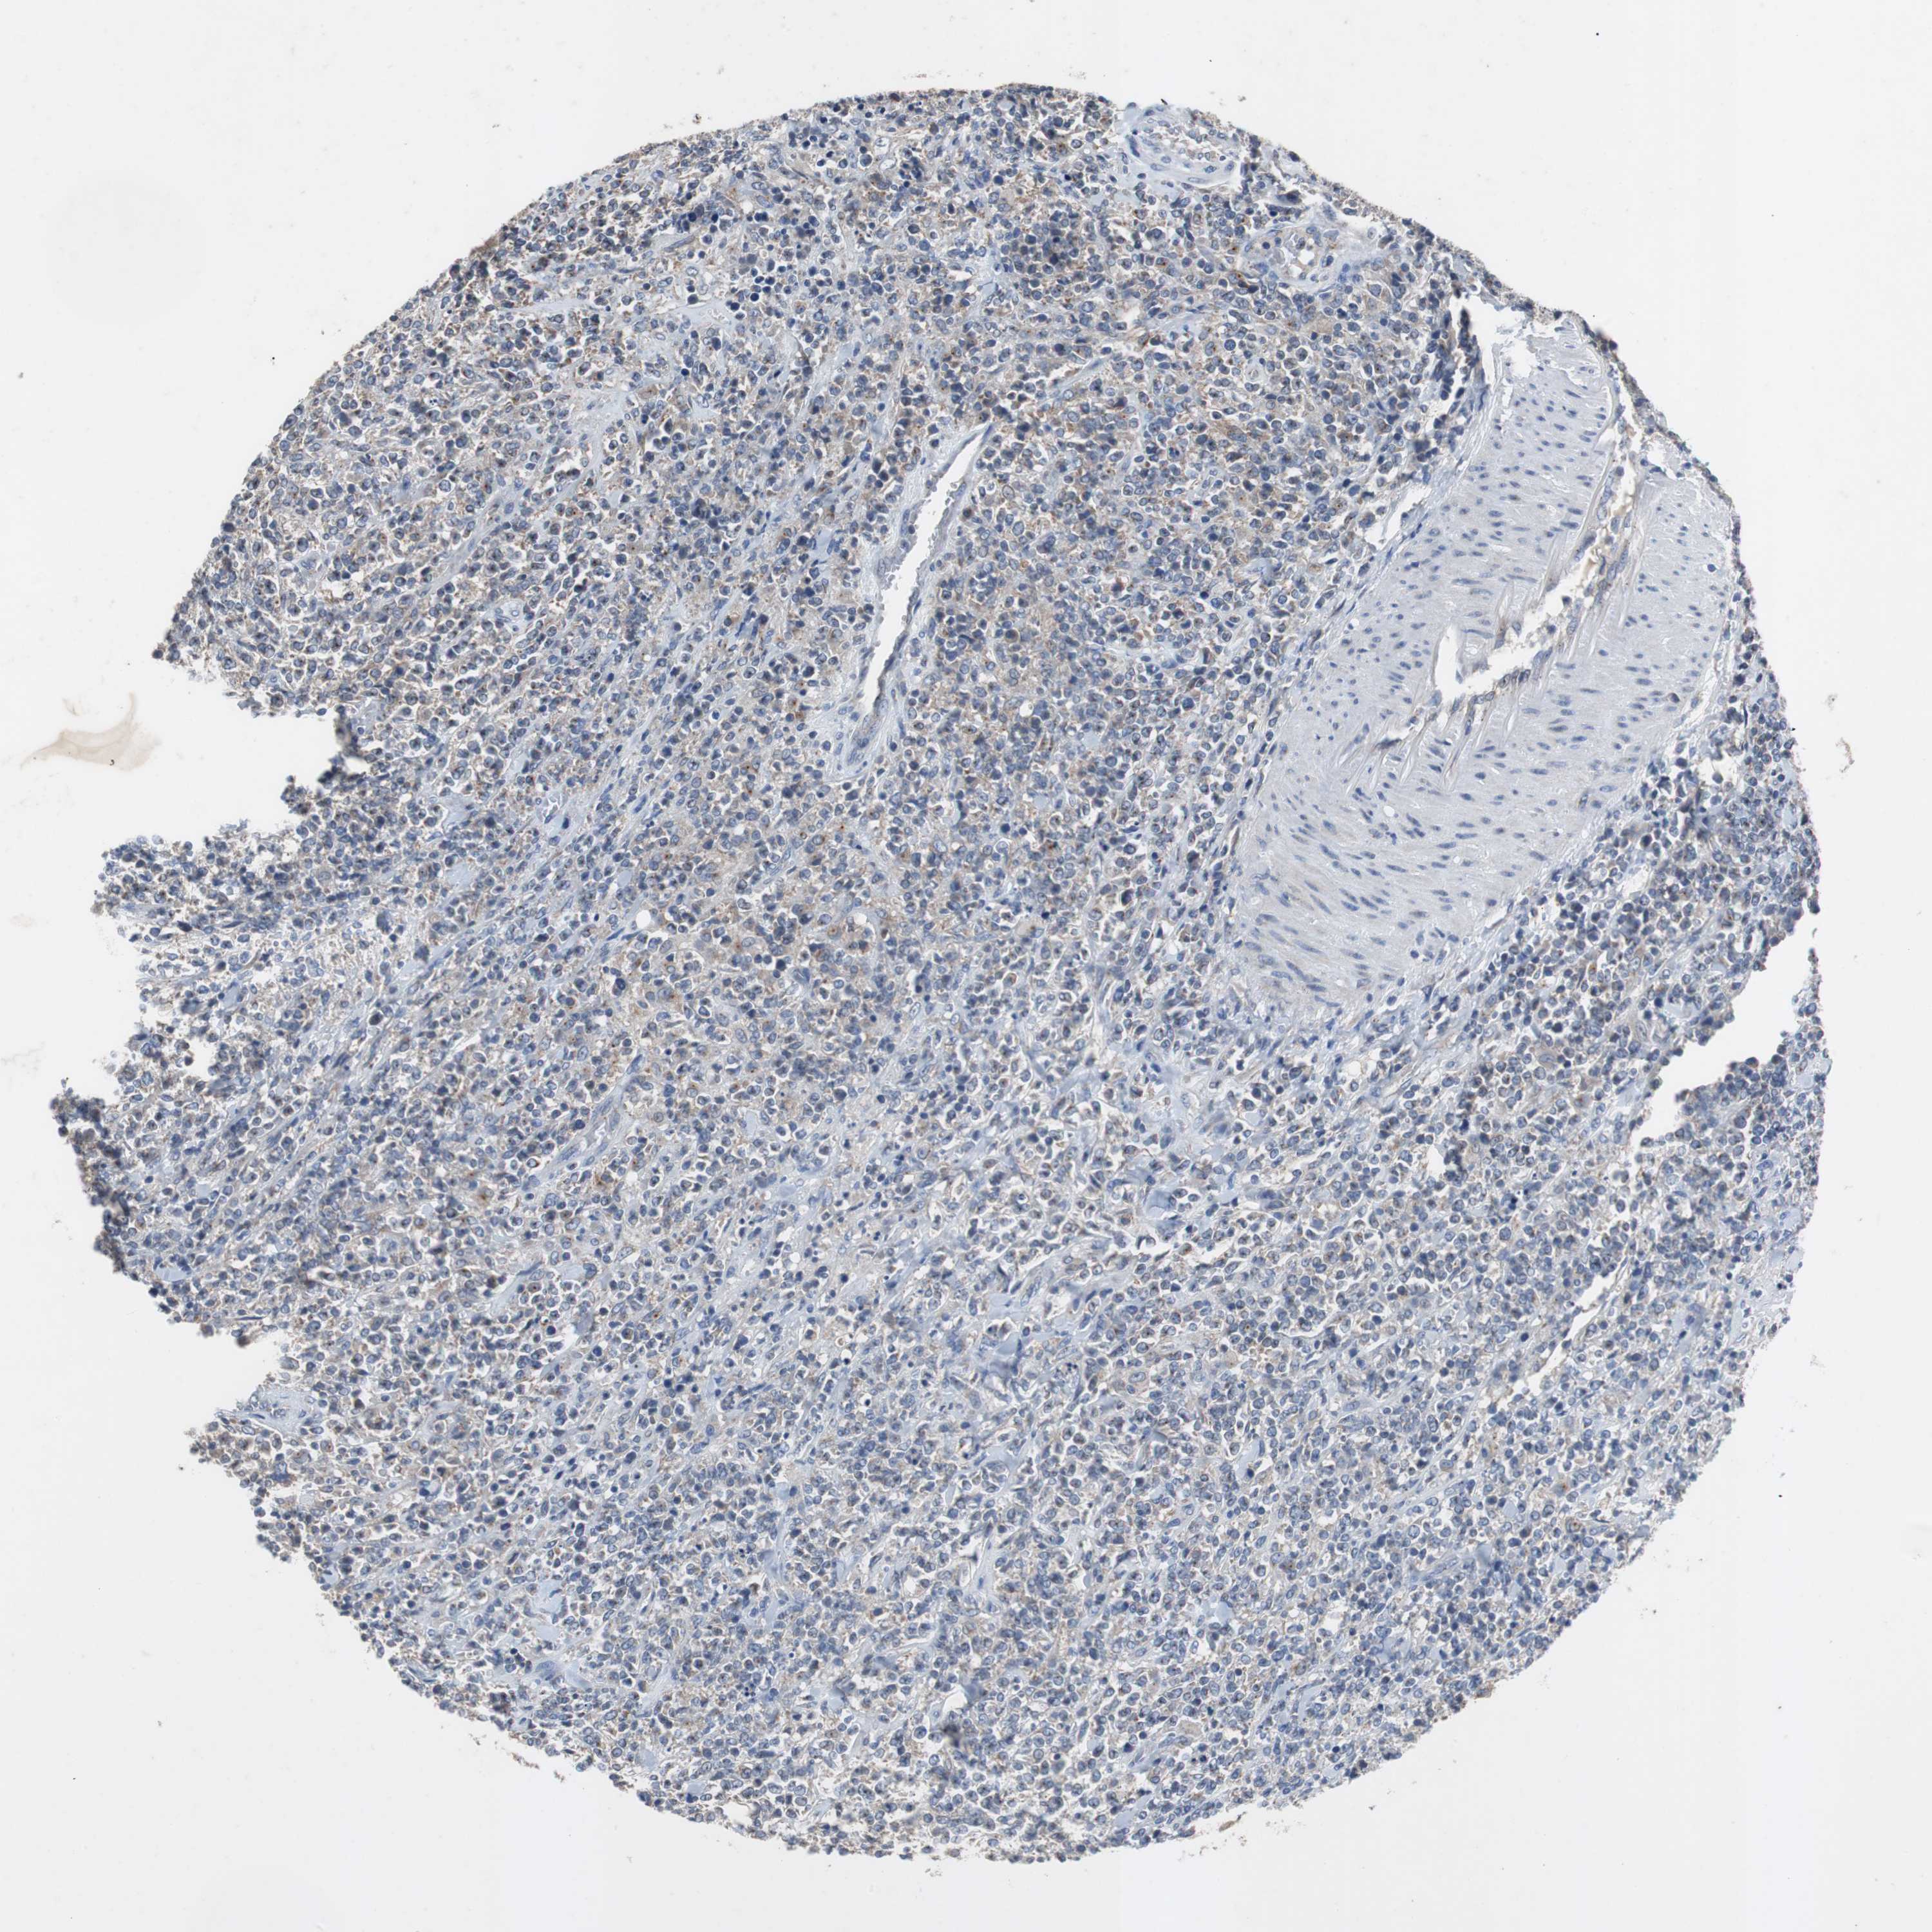

LYMPHOMA - Protein expressioni

A mouse-over function shows sample information and annotation data. Click on an image to view it in a full screen mode. Samples can be filtered based on level of antibody staining by selecting one or several of the following categories: high, medium, low and not detected. The assay and annotation is described here.

Antibody HPA007305

Staining

Low

Weak

<25%

Cytoplasmic/membranous,nuclear

Malignant lymphoma, non-Hodgkin's type, High grade